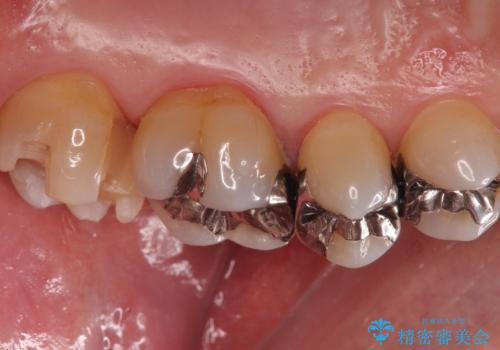

PGA(ゴールド)クラウン、インレーの注意事項(リスク・副作用など)

- インレーおよびクラウンは脱離するリスクがあります

- 形成量はセラミックより少ないですが、歯の形成、修復後に歯に症状が出ることがあります

- 自費診療(保険適用外治療)となります